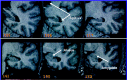

Illustration of the point-counting technique applied to estimate hippocampal volume from MR images of a control (C, top row), patient with left-sided seizure onset (LP, second row), and patient with right-sided seizure onset (RP, bottom row).